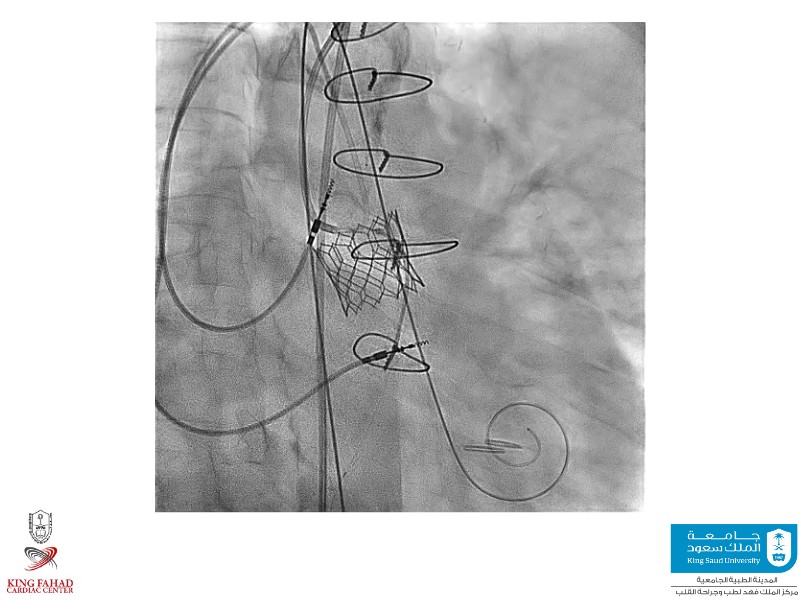

This session helps you anticipate and address complex scenarios such as mitral valve-in-valve, TAV-in-SAV, and valve-in-valve-in-valve procedures. Learn from expert case discussions that explore procedural strategies, technical challenges, and best practices to optimize outcomes in redo structural heart interventions.

- To anticipate and manage second valve scenarios with SAPIEN 3 Ultra RESILIA, including mitral valve-in-valve, TAV-in-SAV, and TAV-in-TAV

- To understand procedural strategies and challenges in complex redo scenarios using SAPIEN 3 Ultra RESILIA